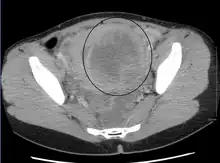

A very large (9 cm) fibroid of the uterus which is causing pelvic congestion syndrome as seen on CT